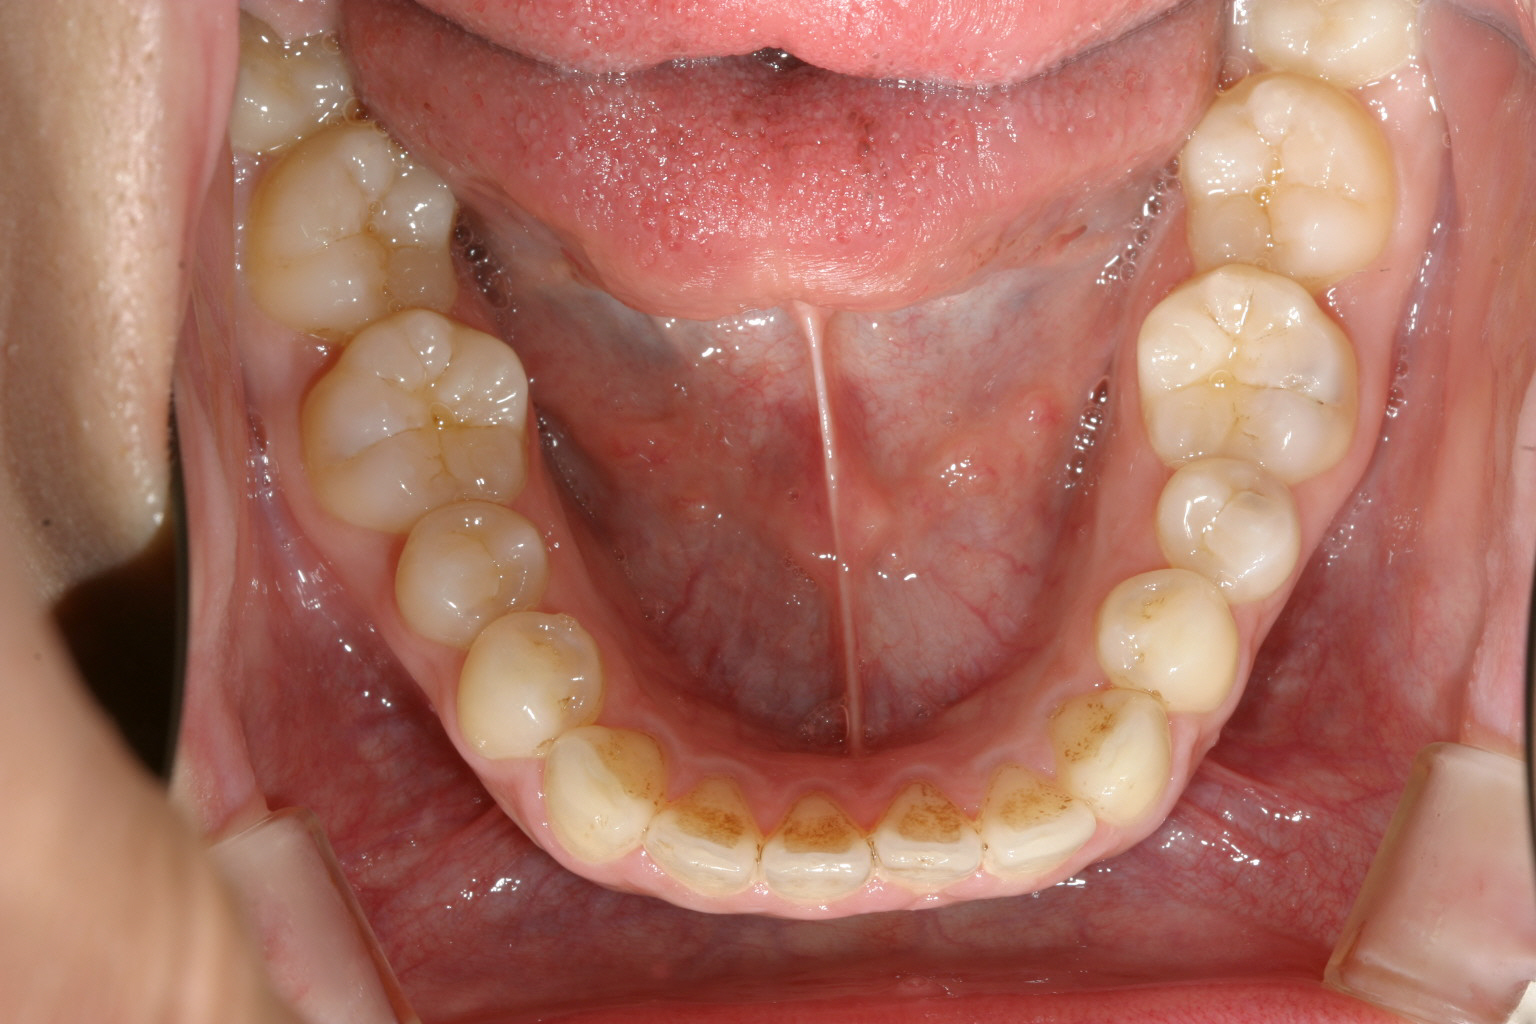

下顎はさほど問題無いみたいです。

下顎はアーチを広げました。